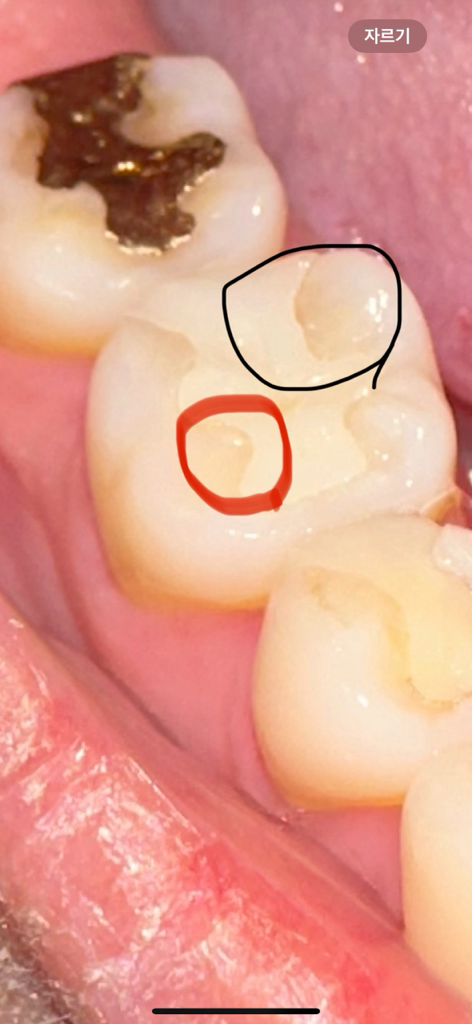

위에 사진이 진료 전 밑에 사진이 진료받은 후 사진입니다 빨간 동그라미 부분 보시면 원래는 저렇게 동그랗게 살짝 파이지않았습니다 보철물이랑 치아 사이 틈이 생긴것같아 전체적으로 다듬어주셨는데 멀쩡한 부분까지 다듬어줬어요.. 이게 올바른진료가 맞나요? 저 부분은 치료를 원하지않았는데 다듬는다는게 이렇게 살짝 파일수도있나요? 전문가분들 도와주세요 ㅠㅠ 다른치과 방문해봐야하나요?